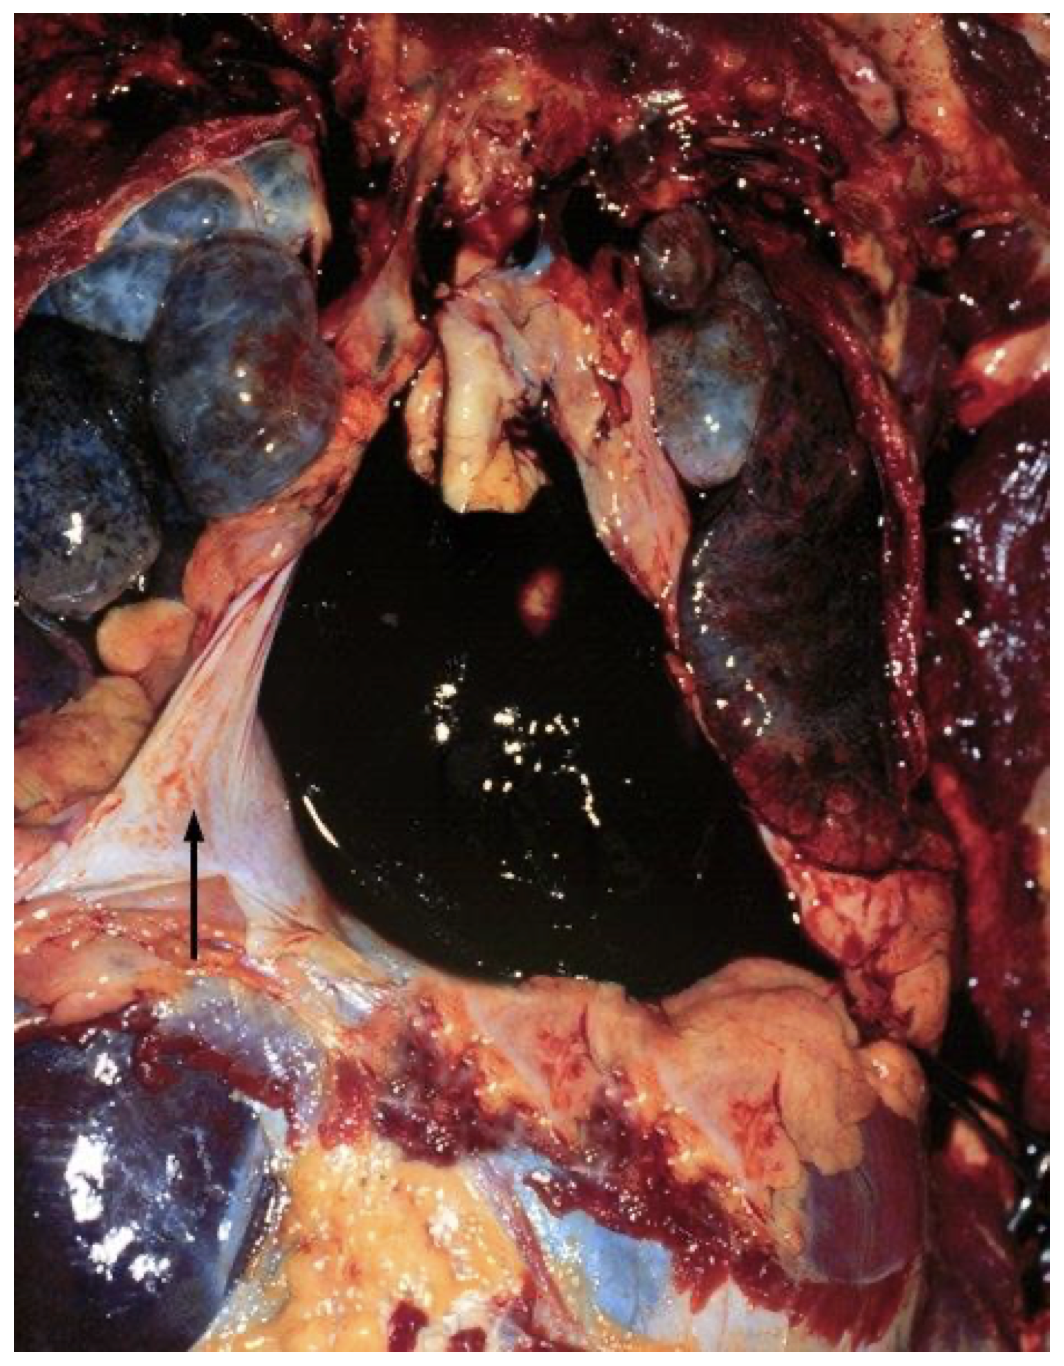

This photograph of the chest cavity at autopsy shows reflected pericardium (arrow) and hemopericardium due to left ventricular rupture of an acute myocardial infarct. The infarct was about 6 days old.

Rupture, left ventricle, with hemopericardium, gross, MI, day 6